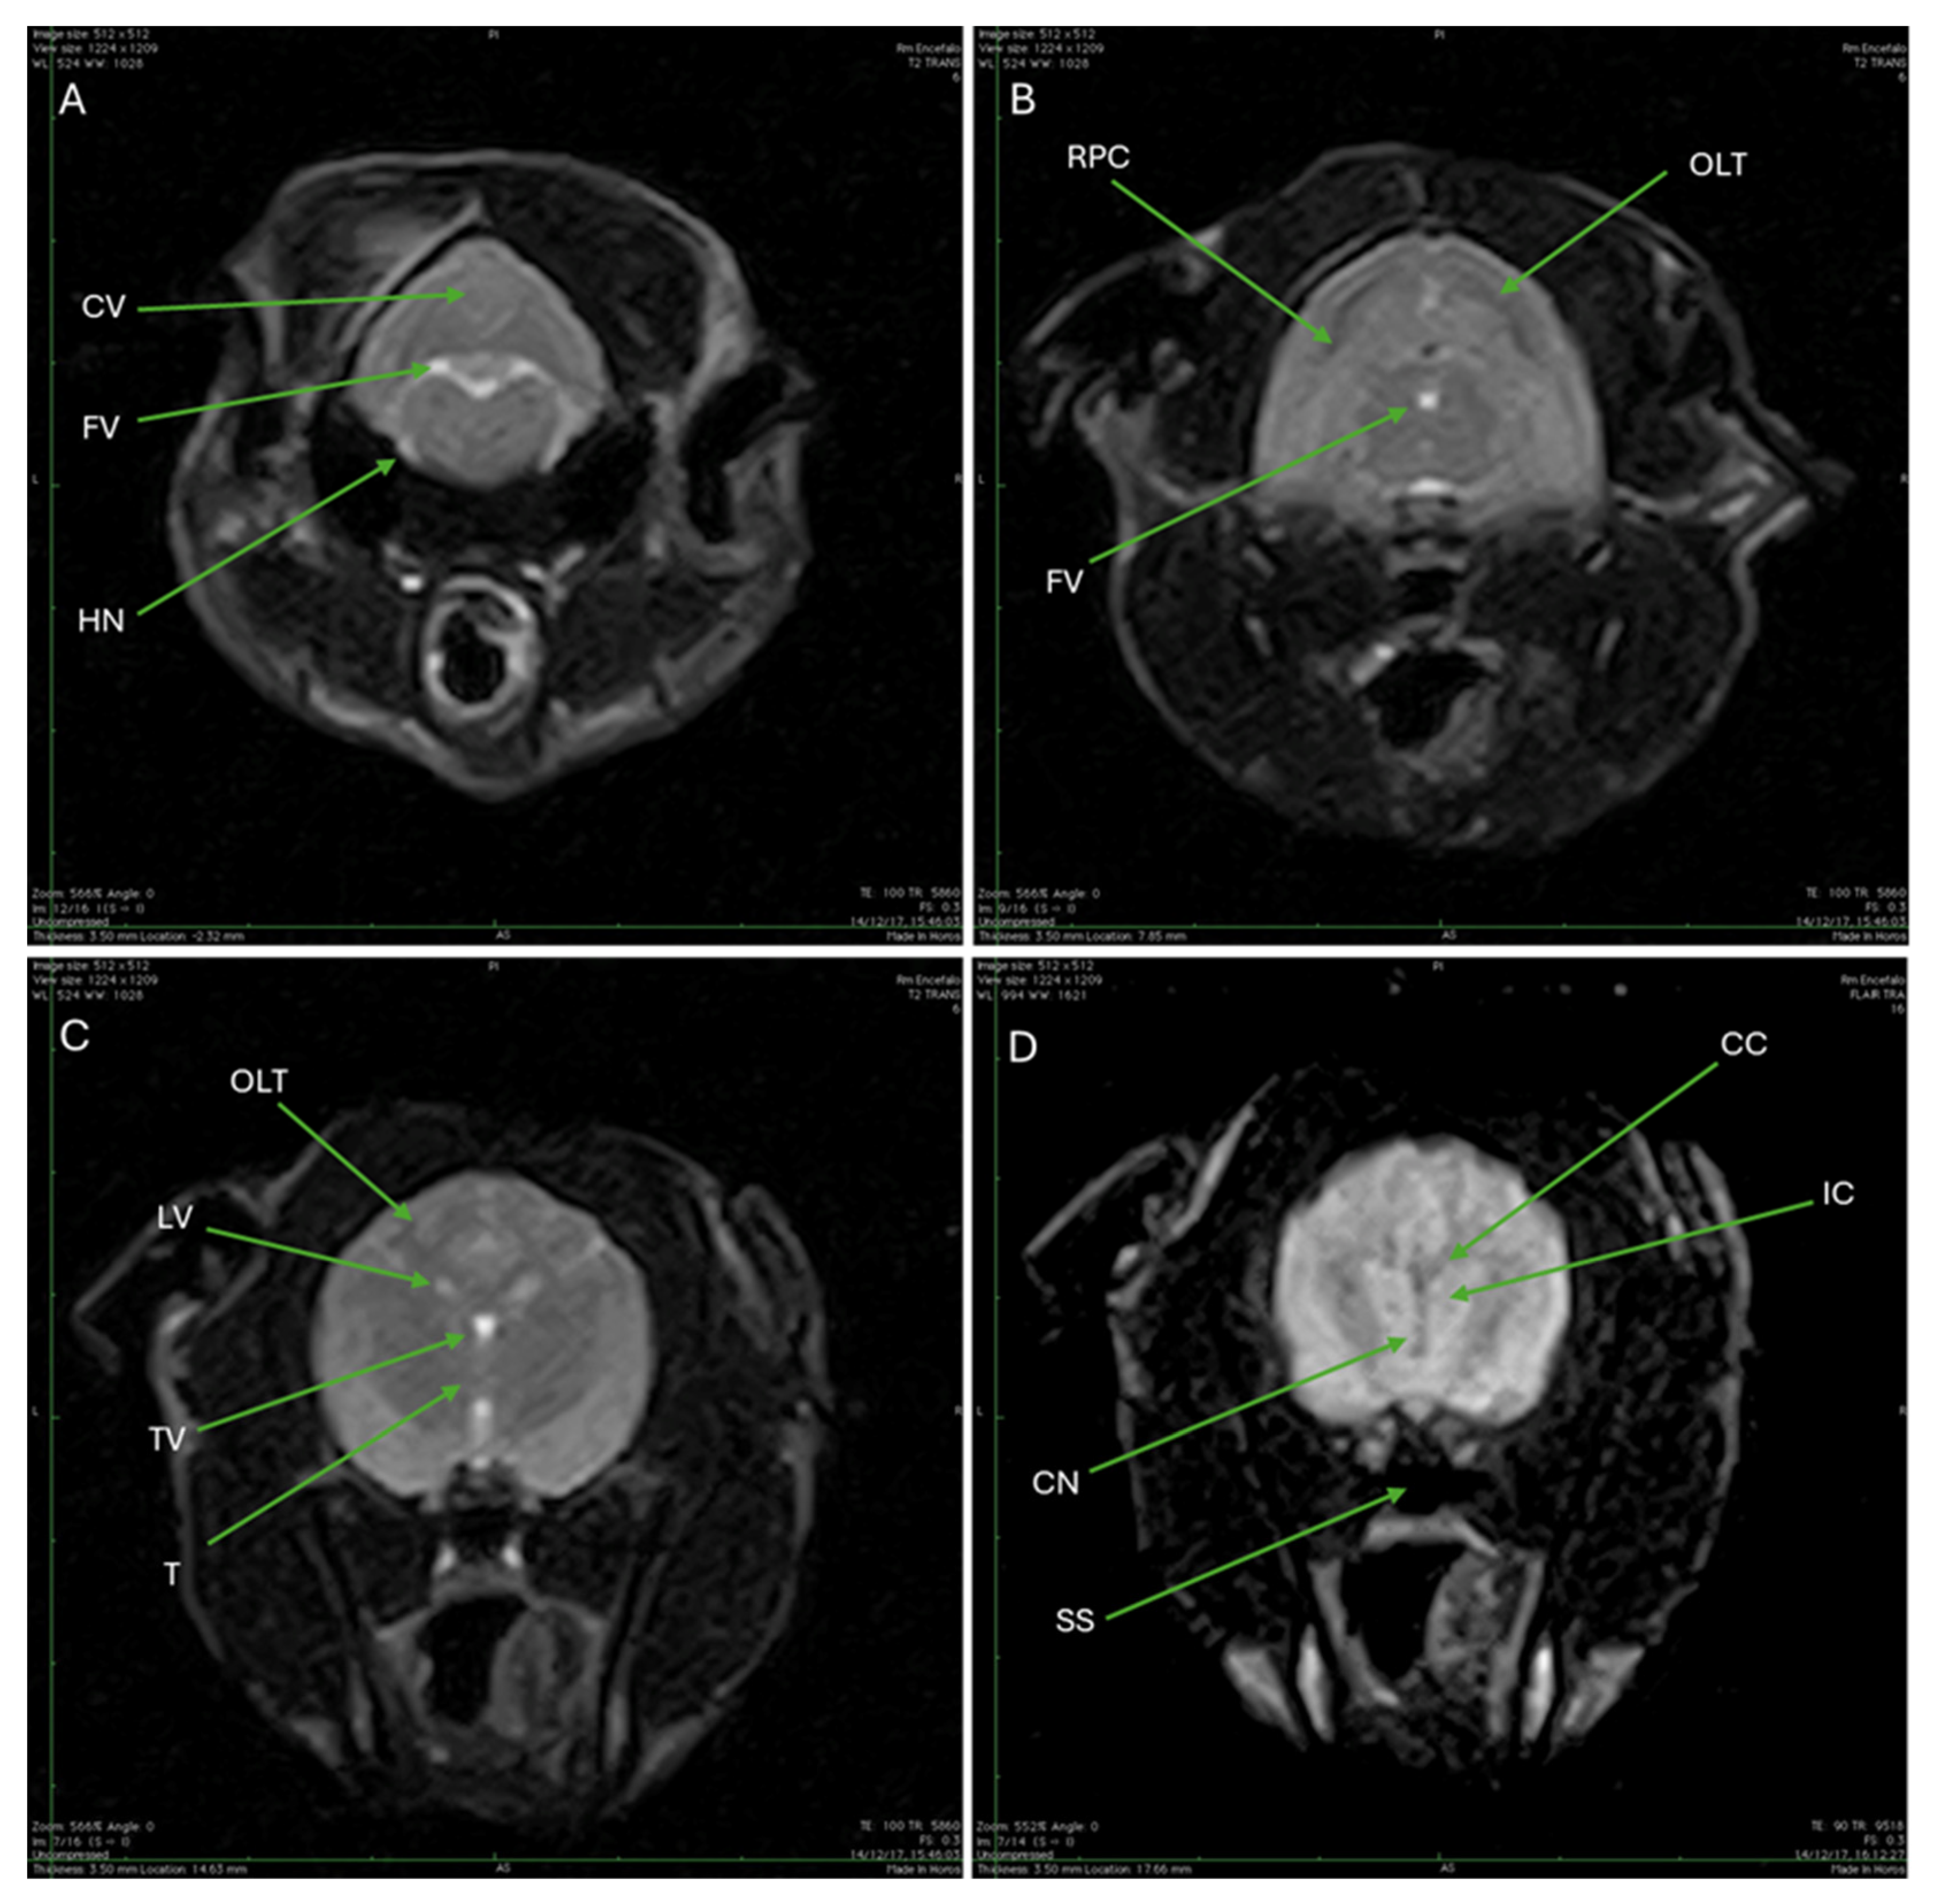

| CV | Cerebellar vermis |

| FV | Fourth ventricle |

| HN | Hypoglossal nerve |

| RPC | Rostral portion of the cerebellum |

| OLT | Occipital lobe of the telencephalon |

| LV | Lateral ventricles |

| TV | Third ventricle |

| T | Thalamus |

| CC | Corpus callosum |

| IC | Internal capsule |

| CN | Caudate nucleus |

| SS | Sphenoid sinus |

4. Discussion